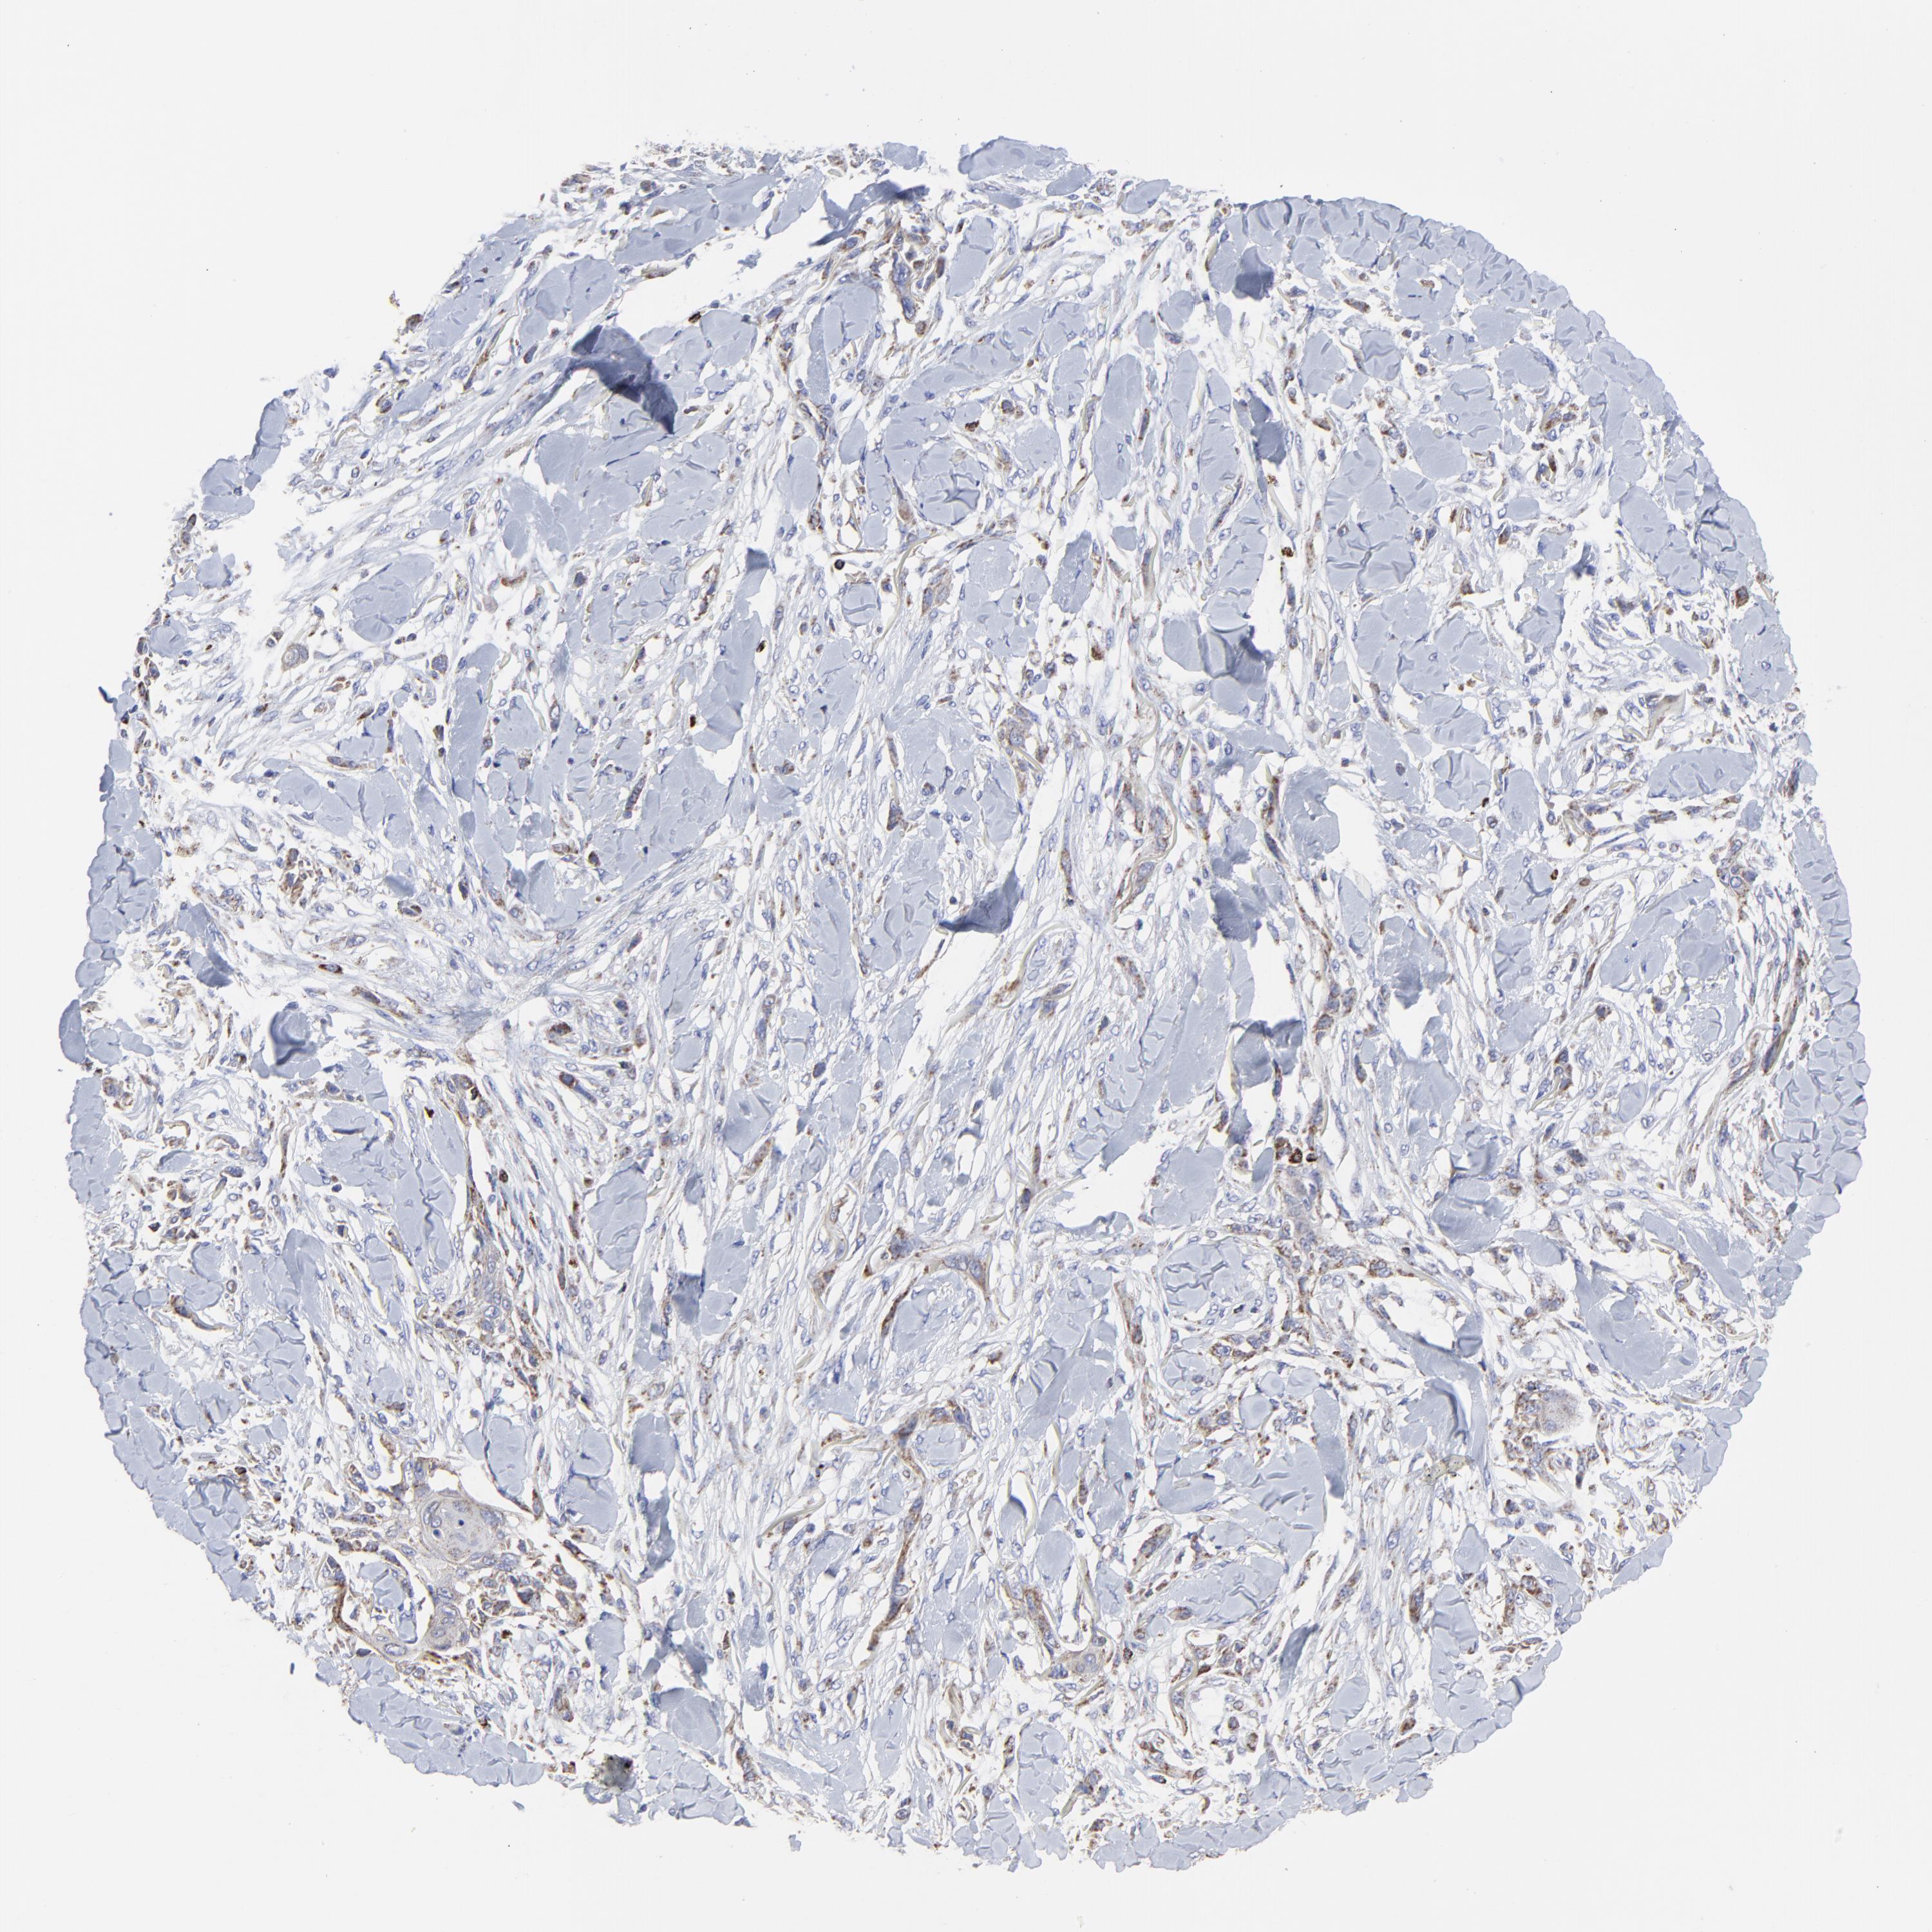

SKIN CANCER - Protein expressioni

A mouse-over function shows sample information and annotation data. Click on an image to view it in a full screen mode. Samples can be filtered based on level of antibody staining by selecting one or several of the following categories: high, medium, low and not detected. The assay and annotation is described here.

Antibody stainingi

Antibody staining in the annotated cell types in the current human tissue is reported as not detected, low, medium, or high, based on conventional immunohistochemistry profiling in selected tissues. This score is based on the combination of the staining intensity and fraction of stained cells.

Each image is clickable and will lead to virtual microscopy that enables deeper exploration of all samples and also displays staining intensity scores, fraction scores and subcellular localization as well as patient and tissue information for each sample.

Antibody CAB026191

Basal cell carcinoma

Adnexal tumor, benign